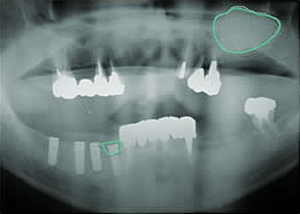

1.・骨つくり

・インプラント15本埋入

ソケットリフト

サイナスリフト

リッジオギュメンテーション

5.終了時レントゲン